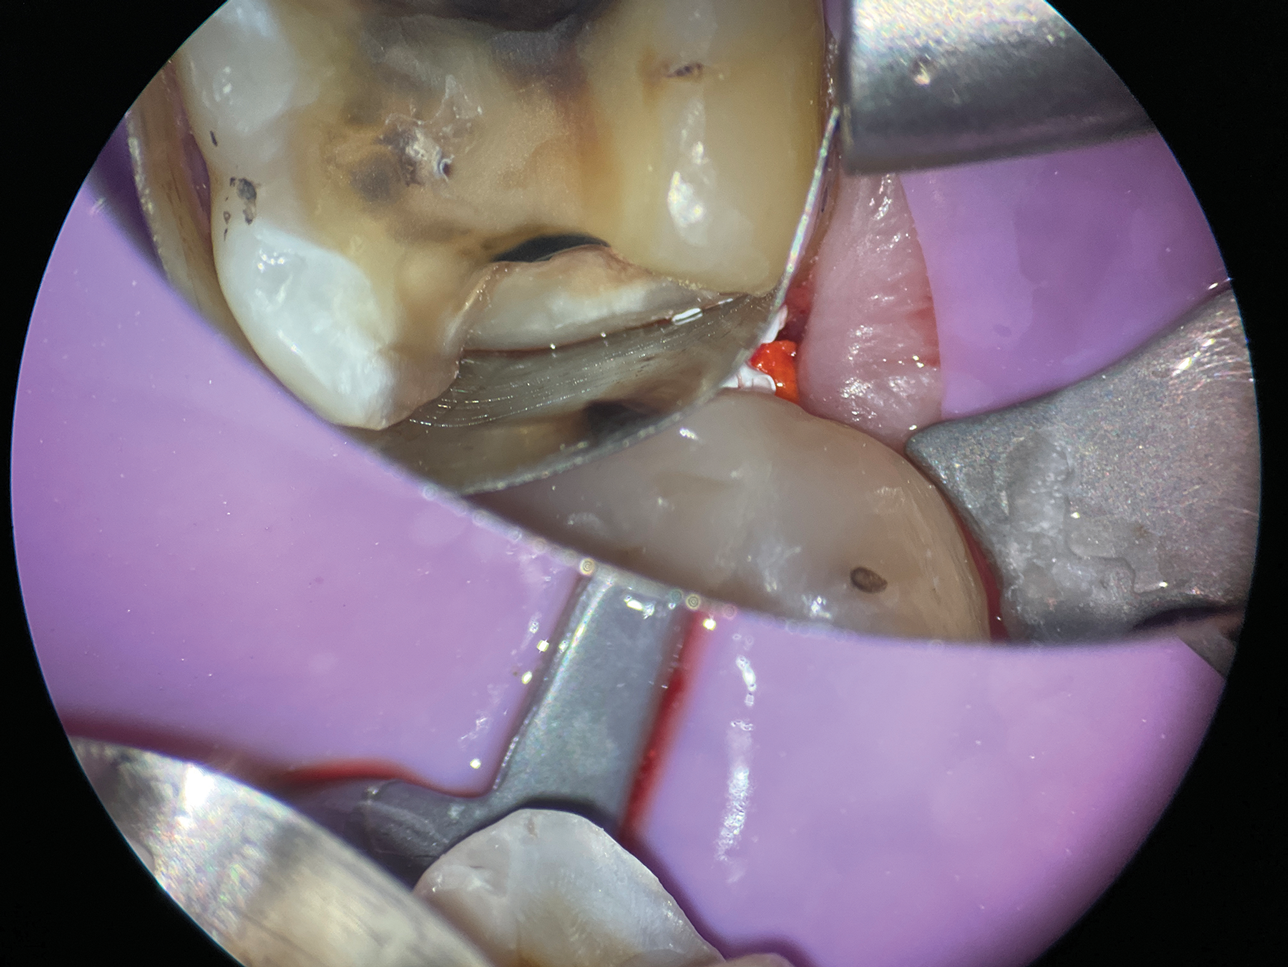

In cases involving extremely deep defects that extend to the bone level, achieving an adequate seal and proper isolation for adhesive procedures can be particularly challenging (Figure 10 and Figure 11). Oftentimes, a single matrix proves insufficient to reach the depth of such defects and effectively shield the cavity from contamination by saliva or blood (Figure 12).

(10.) A close-up distolingual view of a mandibular molar after the removal of caries that extended to the bone level.

Figure 10

(11.) A Willems probe was used to determine that the depth of the margin was approximately 7 mm from the occlusal surface.

Figure 11

(12.) After subgingival placement of a Tofflemire matrix, despite using a wedge and adding additional support with polytetrafluoroethylene tape, fluid infiltration persists through the matrix and margin.

Figure 12